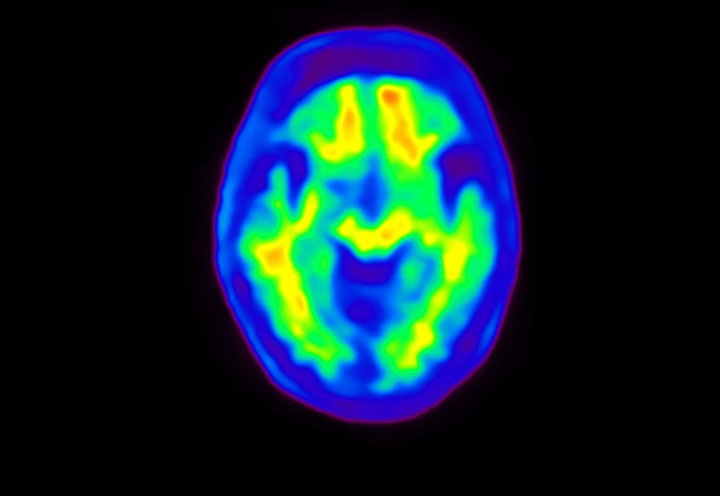

Head / Case4 : Amyloid

Axial

Courtesy : Kindai University Hospital

- Imaging protocol

- Injected dose: 3.21 MBq/kg, 18F-Flutemetamol

- Uptake time: 100 minutes

- Scan time: 20 minutes